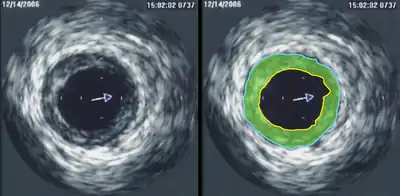

Intravascular ultrasound image of a coronary artery (left), with color-coding on the right, delineating the lumen (yellow), external elastic membrane (blue) and the atherosclerotic plaque burden (green)

Intravascular ultrasound (IVUS) uses a specially designed catheter with a miniaturized ultrasound probe attached to its distal end, which is then threaded inside a blood vessel. The proximal end of the catheter is attached to computerized ultrasound equipment and allows the application of ultrasound technology, such as a piezoelectric transducer or capacitive micromachined ultrasonic transducer, to visualize the endothelium of blood vessels in living individuals.[11]